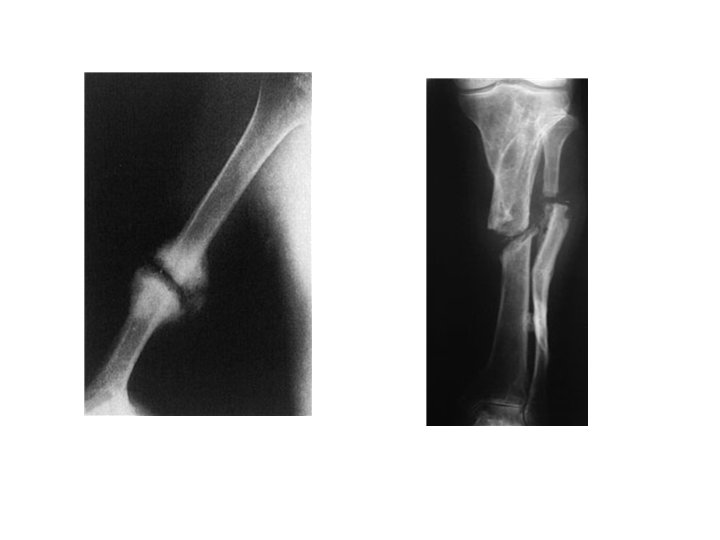

2 -NON-UNION • In a minority of cases delayed union gradually turns into non-union – that is it becomes apparent that the fracture will never unite without intervention. • Movement can be elicited at the fracture site and pain diminishes; the fracture gap becomes a type of pseudoarthrosis. • X-ray The fracture is clearly visible but the bone on either side of it may show either exuberant callus or atrophy. This contrasting appearance has led to nonunion being divided into hypertrophic and atrophic types. In hypertrophic nonunion the bone ends are enlarged, suggesting that osteogenesis is still active but not quite capable of bridging the gap. In atrophic non-union, osteogenesis seems to have ceased. The bone ends are tapered or rounded with no suggestionof new bone formation.

3 -MALUNION When the fragments join in an unsatisfactory position (unacceptable angulation, rotation or shortening) the fracture is said to be malunited. Causes are failure to reduce a fracture adequately, failure to hold reduction while healing proceeds, or gradual collapse of comminuted or osteoporotic bone. • Clinical features • The deformity is usually obvious, but sometimes the true extent of malunion is apparent only on x-ray. Rotational deformity of the femur, tibia, humerus or forearm may be missed unless the limb is compared with its opposite fellow. Rotational deformity of a metacarpal fracture is detected by asking the patient to flatten the fingers onto the palm and seeing whether the normal regular fan-shaped appearance I reproduced • X-rays are essential to check the position of the fracture while it is uniting. This is particularly important during the first 3 weeks, when the situation may change without warning. At this stage it is sometimes difficult to decide what constitutes ‘malunion’; acceptable norms differ from one site to another and these are discussed under the individual fractures